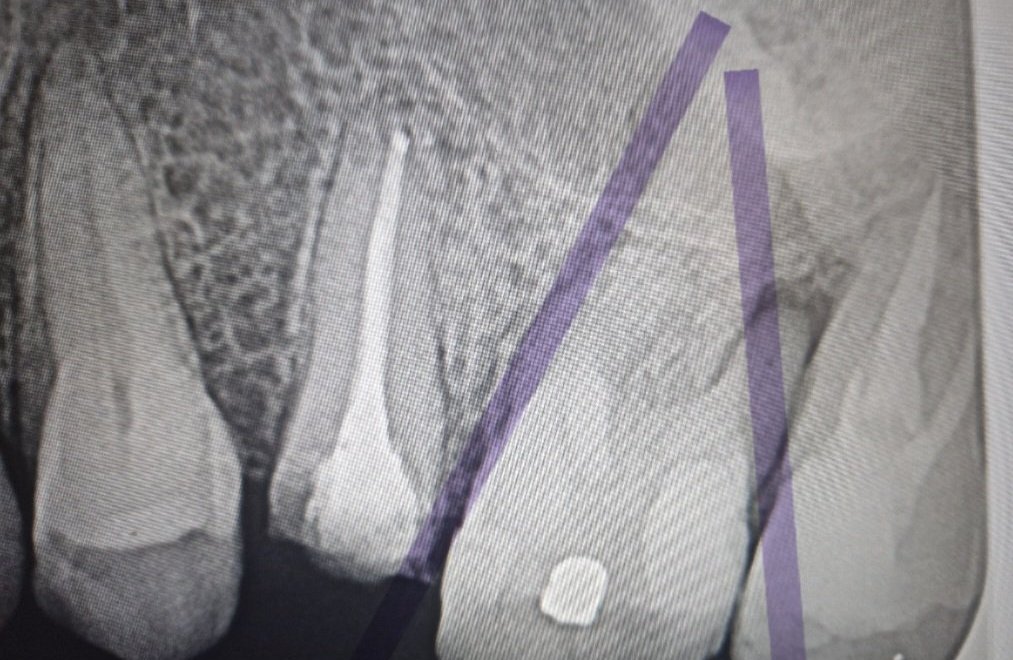

Какво представлява максиларен синузит и как се лекува?